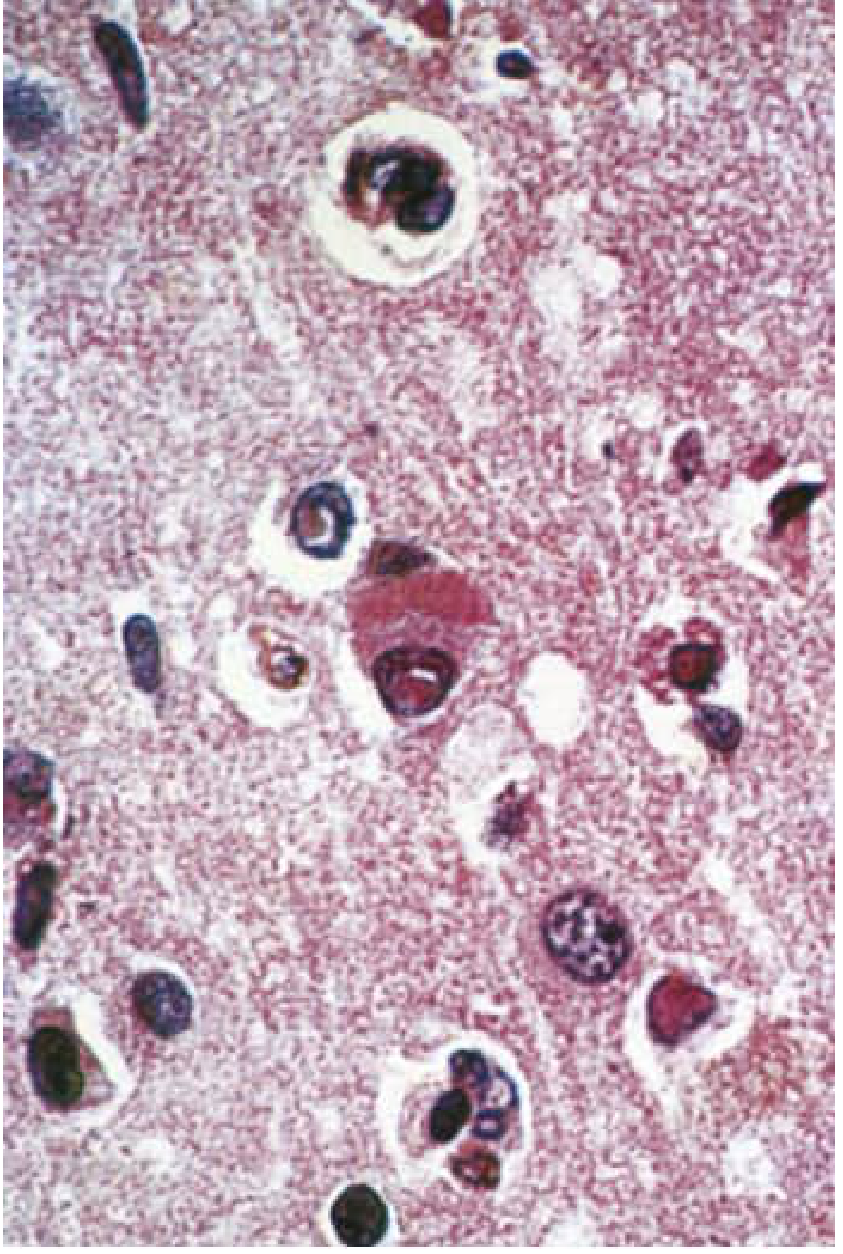

Histopathology

Lesions involve the cerebral cortex and white matter of both hemispheres and the brainstem. The cerebellum is usually spared.

Key findings:

1. Eosinophilic intranuclear and intracytoplasmic inclusion bodies (Cowdry Type A) in neurons and glial cells — the histopathological hallmark

2. Destruction of nerve cells, neuronophagia

3. Perivascular cuffing by lymphocytes and mononuclear cells

4. White matter: degeneration of myelinated fibers (both myelin and axons) + fibrous gliosis → "sclerosing encephalitis"

5. Electron microscopy: measles nucleocapsids in inclusion-bearing cells

Cerebral cortex in SSPE — Cowdry-type A intranuclear inclusion in a pyramidal neuron plus cigar-shaped cytoplasmic inclusion; Cowdry A inclusions also present in glial cell nuclei. H&E ×350. (Bradley & Daroff's Neurology)

Fig. 78.8 — Cerebral cortex in SSPE: Cowdry-type A intranuclear inclusion and cigar-shaped cytoplasmic inclusion in a pyramidal neuron. Glial inclusions also visible. H&E ×350. (Bradley & Daroff's Neurology in Clinical Practice)